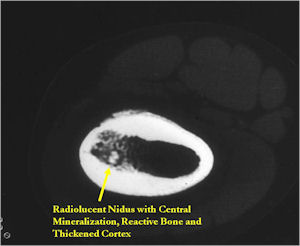

CT Scan:

- Well defined nidus with a smooth peripheral margin; +/- mineralization (CT more sensitive than XR and MRI for detecting mineralization); CT is better for detecting nidus in presence of exuberant sclerosis

- Most osteoid osteomas are intracortical in origin but can also occur in the medullary canal or subperiosteal

- Periosteal bone is solid, rarely lamellated

- Cortical and subperiosteal osteoid osteomas are usually associated with much more reactive sclerosis than medullary tumors

- The periosteal reaction is continuous and often appears as cortical thickening (benign appearing reaction)